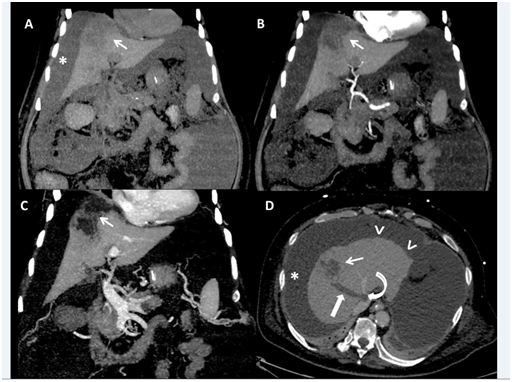

A sixty five-year-old male, diagnosed as a case of non-alcoholic steato-hepatitis related compensated chronic liver disease since one year, presented to us with complaints of progressive non cholestatic jaundice without prodrome for a period of 20 days. This was followed by painless abdominal distension and decreased urine output. The patient subsequently developed altered sensorium in a period of two days associated with excessive drowsiness along with high grade fever. He was teetotaller with history of type II diabetes since 12 years and had no other co-morbidities .There was no history of blood transfusions, alternative medicine intake. He was intubated outside and shifted to us on ventilator and inotropic support. Labs results showed haemoglobin 9.6 g/dL, white blood cell 27880/mm3 ,platelet 98000/mm3, BUN 93 mg/dL ,serum creatinine 4.01mg/dL ,severe metabolic acidosis with arterial lactate of 4.5 mmol/L. Liver function tests showed AST 40 U/L, ALT 32 U/L, alkaline phosphatase 129 U/L, GGT 45 U/L and bilirubin of 1.18 mg/dl. PT INR was 4.5 with very low fibrinogen. Acute viral markers (hepatitis A & E) and hepatitis B and C serology were negative, malaria antigen and leptospira IgM were nonreactive. Autoimmune markers were negative. Ultrasonography(USG) showed features of liver cirrhosis with portal hypertension. It also showed ill-marginated ill-defined subtle hypoechoic lesion in superior segment of right lobe with hypoechoic thrombus in right hepatic vein protruding into the inferior vena cava (Patients had been regularly following and his USG 3 months ago did not show any SOL). Ascitic fluid white cell count (842 cells/dL) with 72% neutrophils suggested spontaneous bacterial peritonitis. The α-fetoprotein level was 82 ng/mL. CA 19-9 and CEA were normal. Continuous renorenal replacement was initiated along with aggressive medical management for metabolic acidosis and hemodynamic instability. Contrast CT scan confirmed liver cirrhosis, gross ascites and splenomegaly (Figure 1) it also revealed a hypo-dense, ill-marginated, non-enhancing, sub-capsular mass in segment VII and VIII with non-enhancing, occlusive skip thrombi in the right hepatic vein protruding into IVC, occlusive thrombus of the right and main portal veins protruding into the left portal vein and retro-pancreatic splenic vein. Multiple enlarged necrotic pre-vascular, anterior peridiaphragmatic and pericardial lymph-nodes were also seen (Figure 2). In view of coagulopathy ,hemodynamic instability and cirrhosis it was decided to do the internal mammary lymph node after TEG based correction of coagulopathy . It showed (Figure 3) cells with biphasic neoplasm with epithelioid and spindle cells, marked nuclear pleomorphism with giant and bizarre nuclei and a high Ki-67 index. IHC showed strong coexpression of PanCK and Vimentin and was negative for LCA, CK7, CK20, TTF1, Hep Par-1, Glypican 3, p40. These features were suggestive metastatic PHSC. Meanwhile patient’s condition rapidly worsened over period of 5 days with development of multi organ failure. He eventually succumbed on the seventh day of hospital stay.

Figure 2 Multiple enlarged necrotic pre-vascular, anterior peridiaphragmatic and pericardial lymph-nodes.